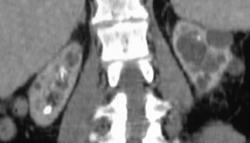

End Stage Kidney Disease (chronic Pyelonephritis)